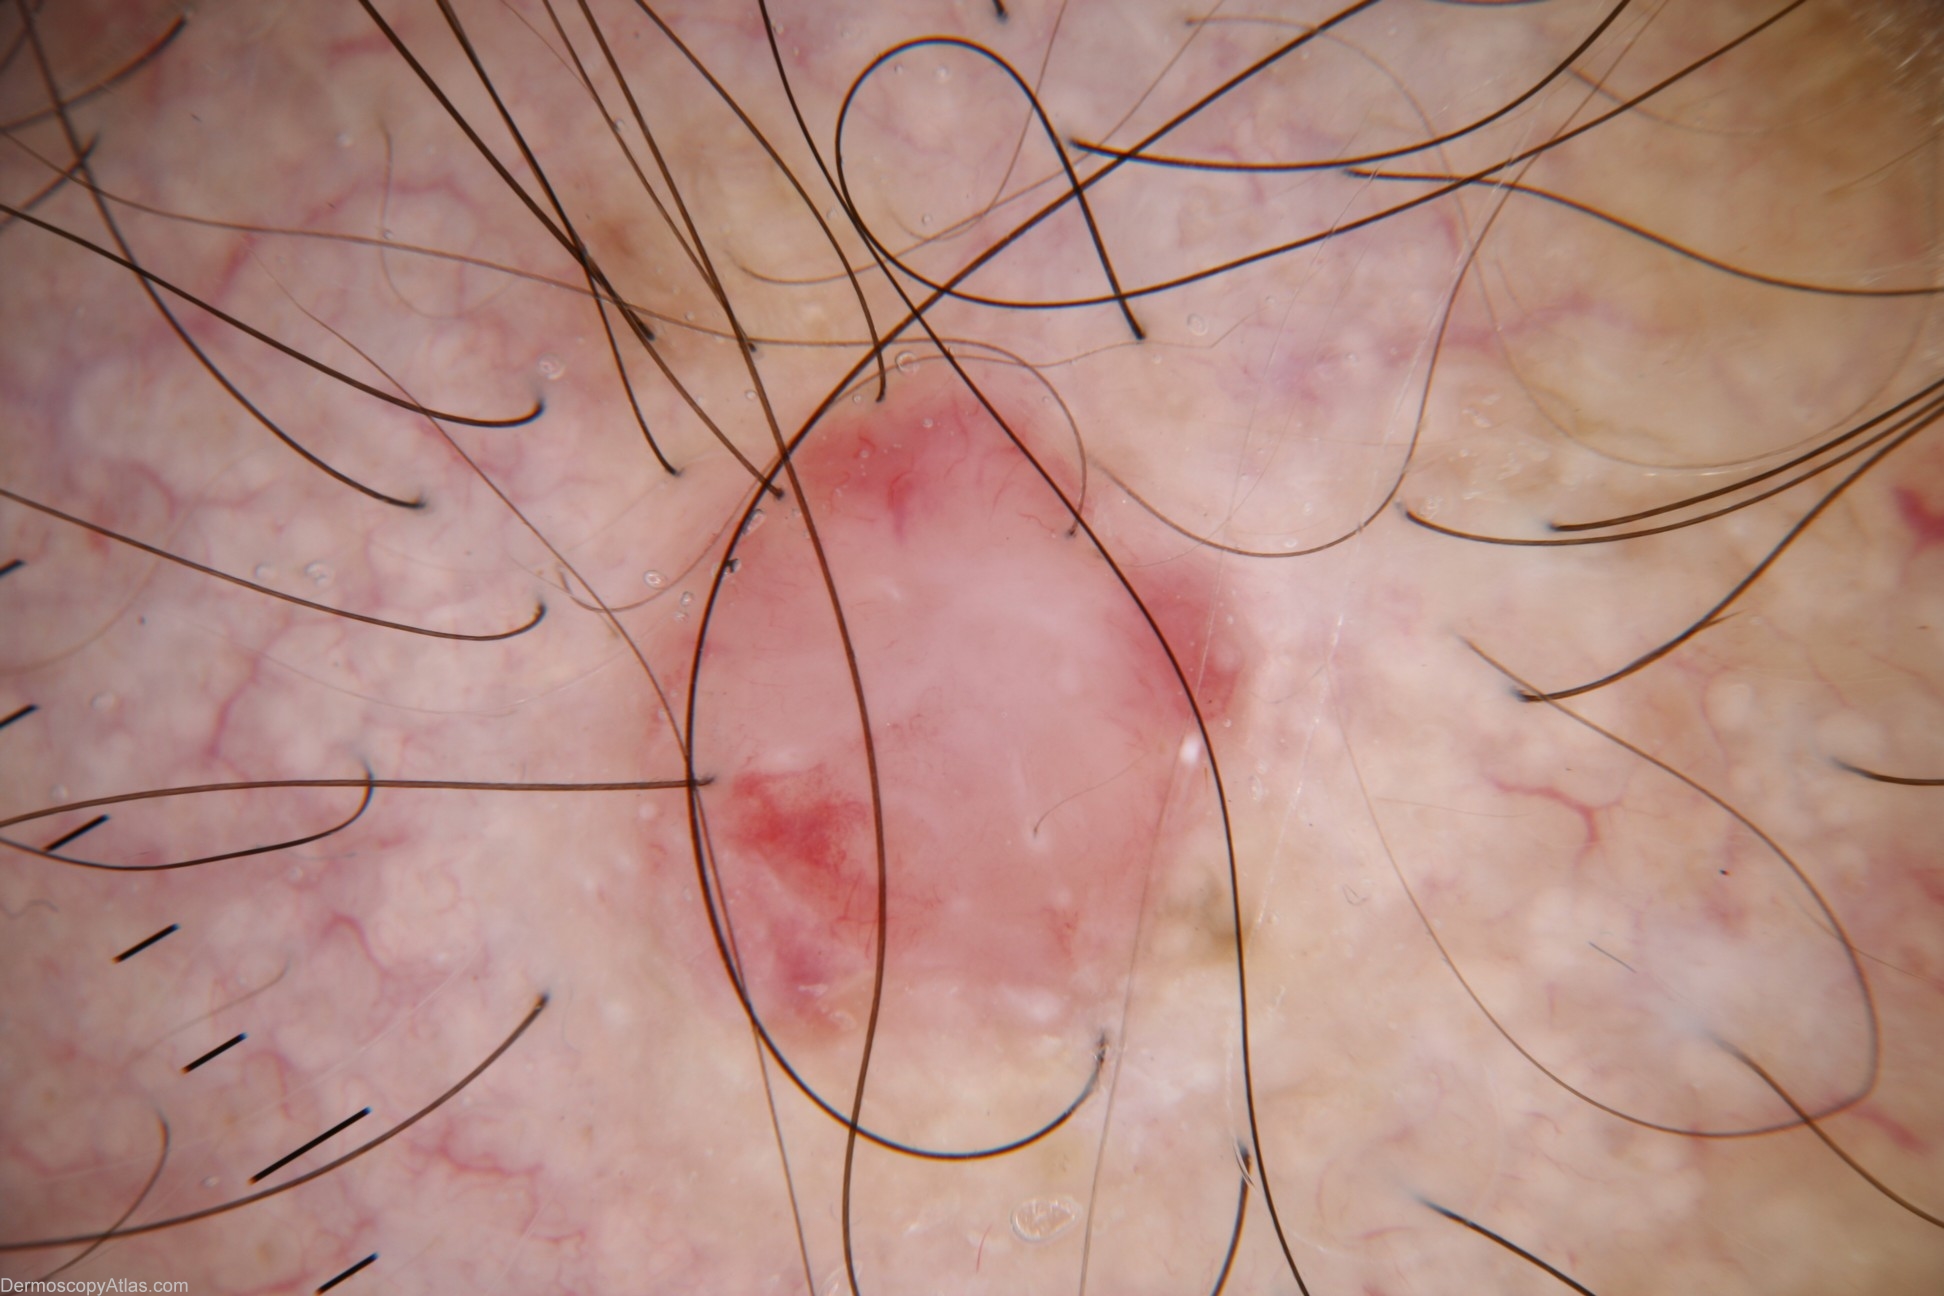

Description: Dermoscopy - This lesion is apigmented and structureless. The only dermoscopic features are a distinctive cherry colour and a few fine blood vessels